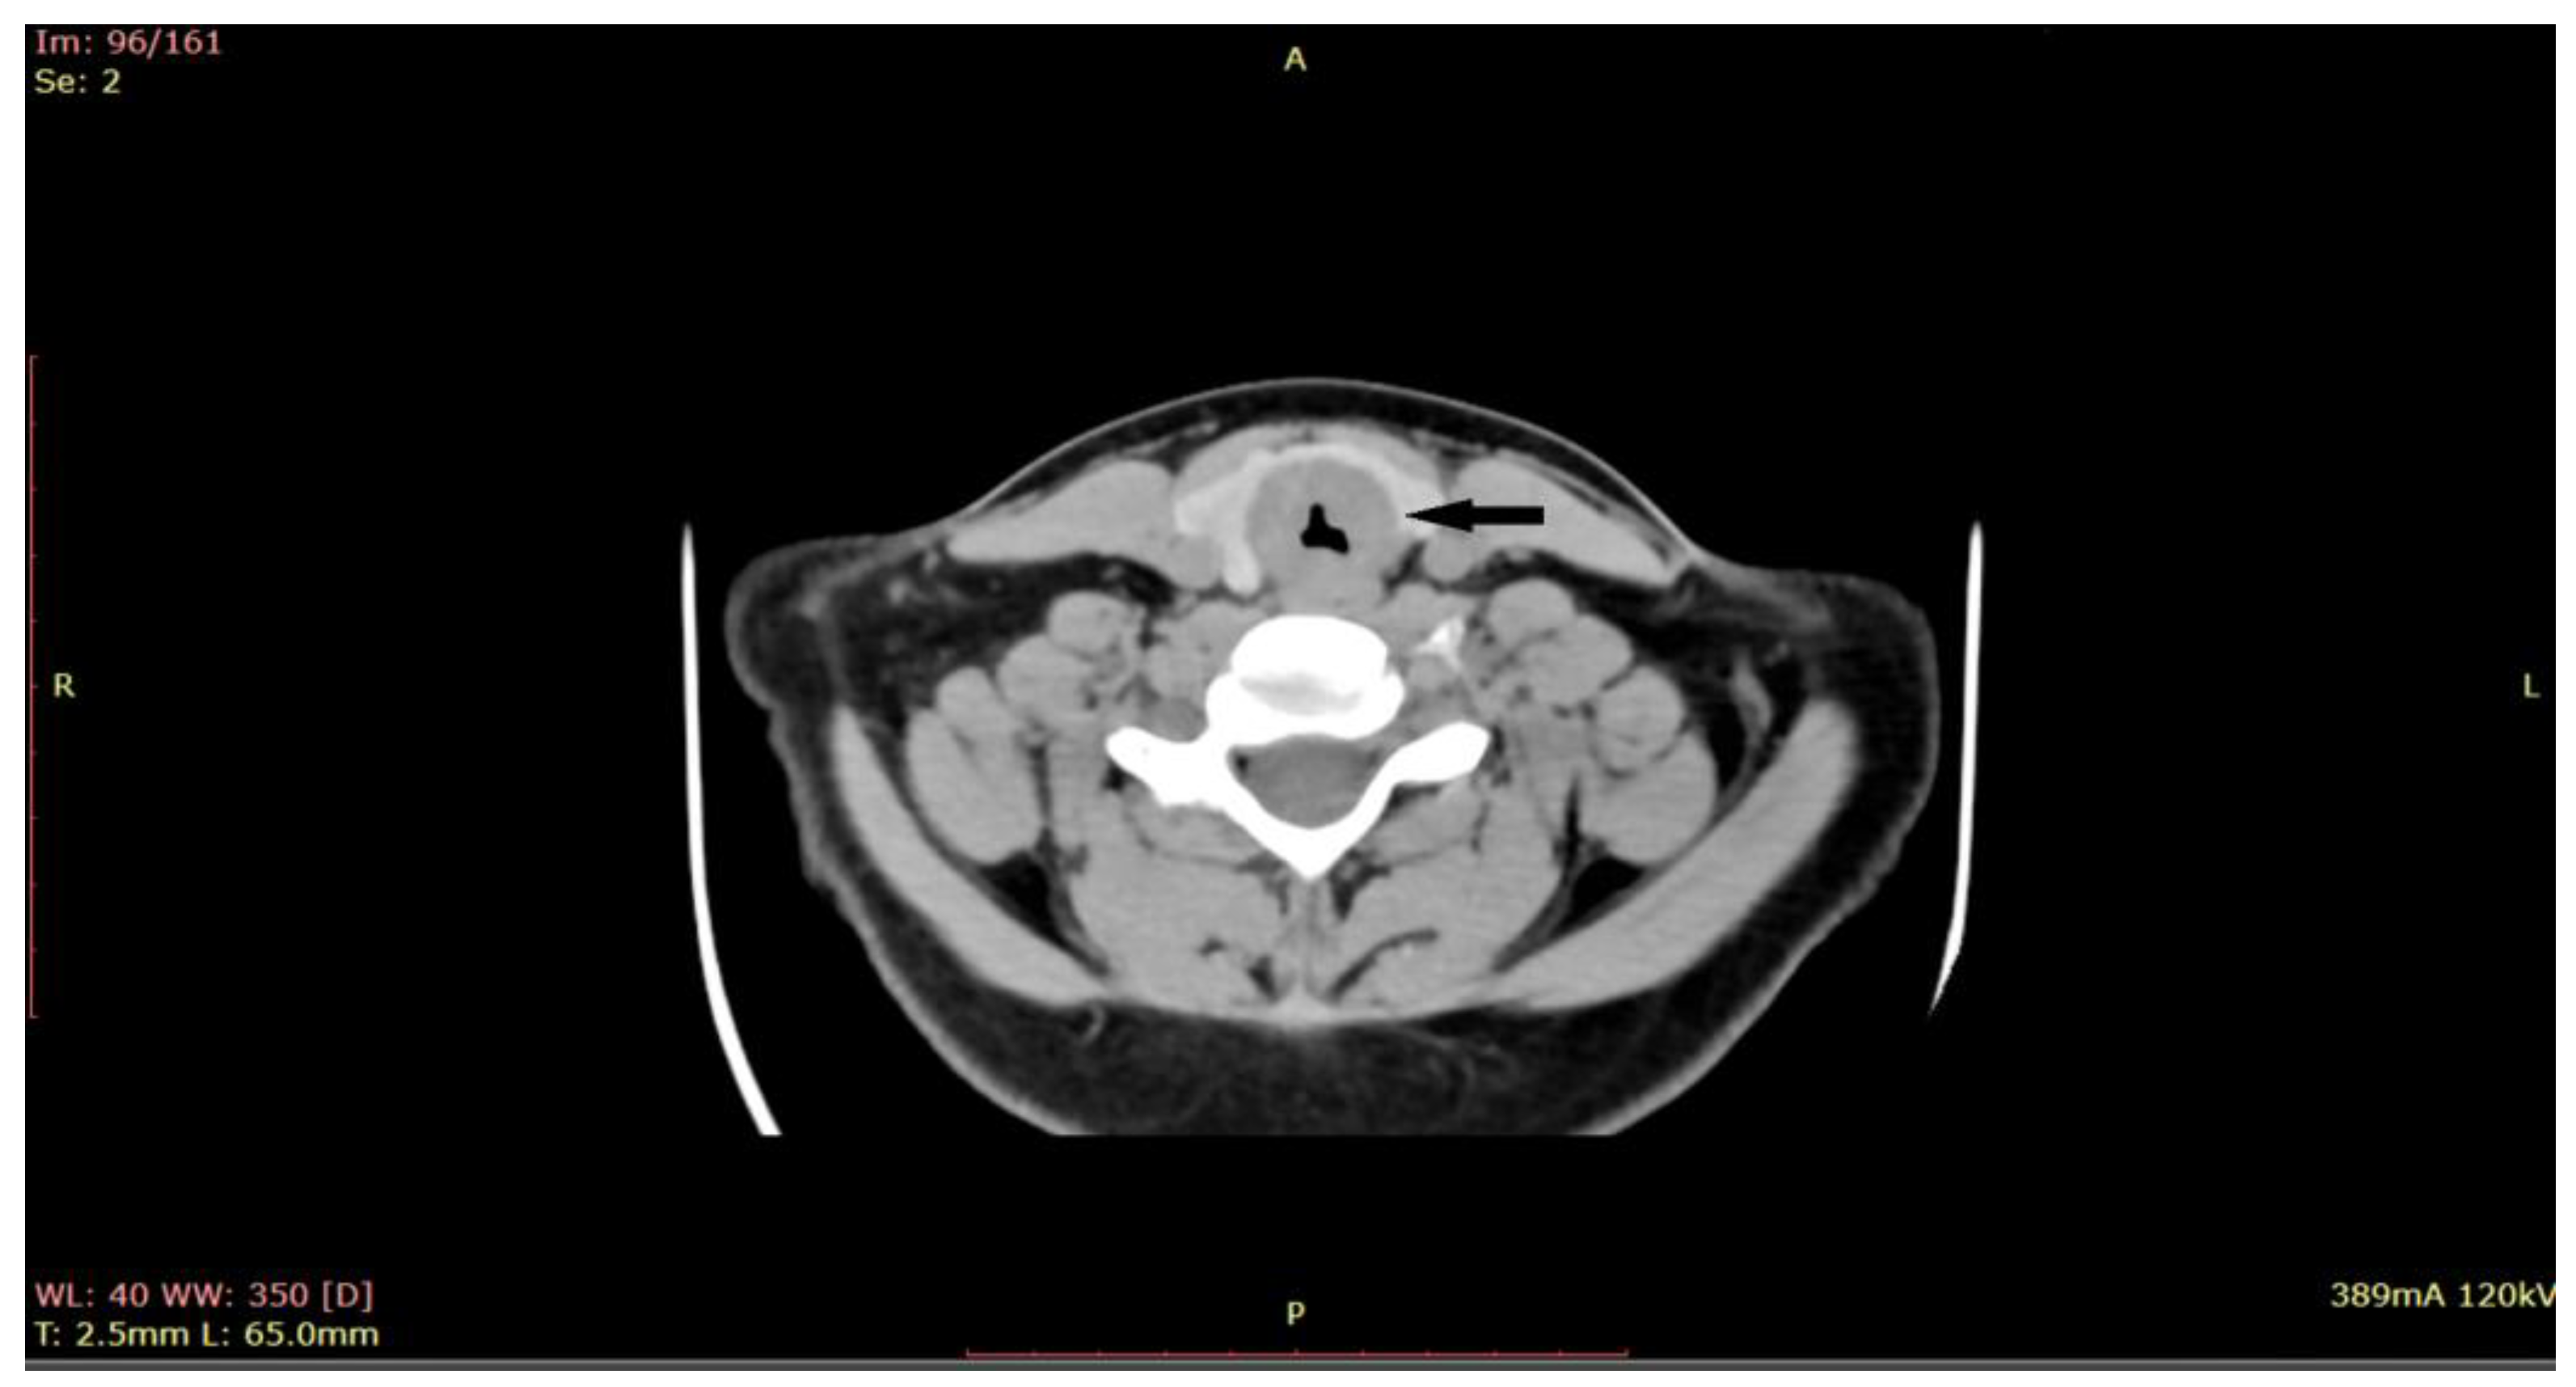

Given the critical nature of the patient’s condition, an immediate intervention was performed before sending the patient for a CT scan. Emergency tracheostomy was performed to secure the airway. However, during the operation, the patient developed a spontaneous left pneumothorax, which necessitated pleural drainage. The aim of the procedure was to secure the airway, relieve respiratory distress, and obtain a biopsy for further diagnosis. Once the patient’s condition stabilized after the pleural drainage, a biopsy of the subglottic tumor was obtained through direct laryngoscopy. During the direct laryngoscopy procedure, a tumor formation was observed in the subglottic region, involving the first tracheal ring. On examination, the tumor appeared slightly indurated, with smooth local mucosa. It circumferentially covered the subglottic area with marked narrowing of the respiratory space. A computed tomography (CT) scan was performed (Figure 2), which showed subglottic mass involving the trachea, with marked circumferential and slightly asymmetrical thickening of the laryngeal walls, from a plane passing through the arytenoid cartilages, involving the cervical trachea until the distal space C7-T1, with marked intraluminal stenosis (71%) and compression of the thyroid lobes.

Figure 2.

CT of the larynx shows a subglottic submucosal mass with marked intraluminal stenosis (at the arrow)-axial plane.